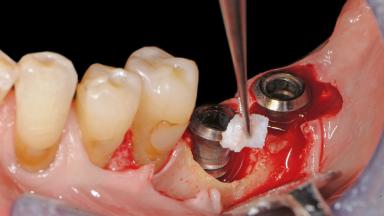

Paolo Casentini demonstrates that peri-implantitis can be successfully treated even at an advanced stage. He discusses a case in which the existing implants and prostheses were both retained while regenerating the defect and creating a band of keratinized tissue. A 69-year-old female patient was referred by her general dentist for evaluation of a recurrent infection at previously placed and restored implants in the posterior left mandible. The patient’s chief complaint was recurrent swelling and pain in the molar region of the left posterior mandible with discomfort during brushing in the same area. The patient reported receiving two implants (36 and 37) nine years earlier.